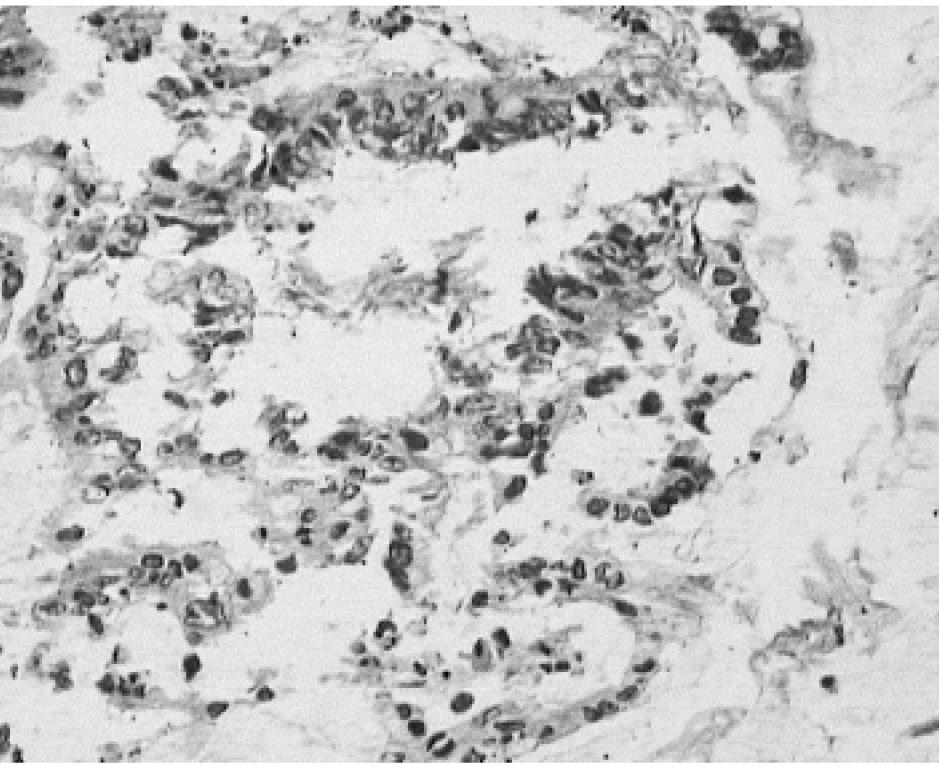

Через месяц выполнено чрескожное чреспеченочное стентирование гепатикохоледоха с установкой металлического саморасширяющегося стента Hanarostent SHS-10-100-060 (размер стента 10 на 100 мм). На первом этапе процедуры также была проведена повторная эндобилиарная биопсия из области опухолевой стриктуры. По данным гистологического исследования выявлен некроз опухолевой ткани, отмечена III степень лечебного патоморфоза по классификации O. Dworak и соавт. (рис. 5) [5].

Рис. 5. Микрофото. Ув.×250. Окраска гематоксилин и эозин. Некроз холангиокарциномы после ФДТ — III степень лечебного патоморфоза по классификации O. Dworak и соавт. [5]